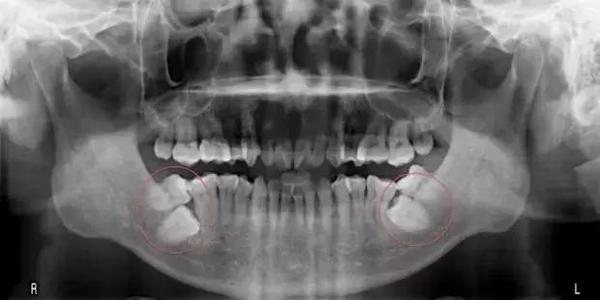

▲環口X光片:紅圈處的第二大臼齒及智齒歪斜,影響大臼齒牙冠及牙周健康。